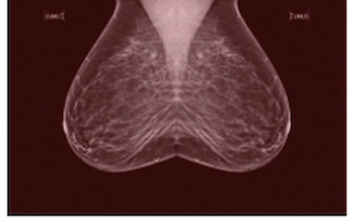

In a large retrospective study involving over 523,000 digital breast tomosynthesis (DBT) exams and over one million digital mammography (DM) exams, researchers found that DBT was associated with significantly lower recall rates but showed no advantage over DM in the diagnosis of interval or advanced breast cancer.